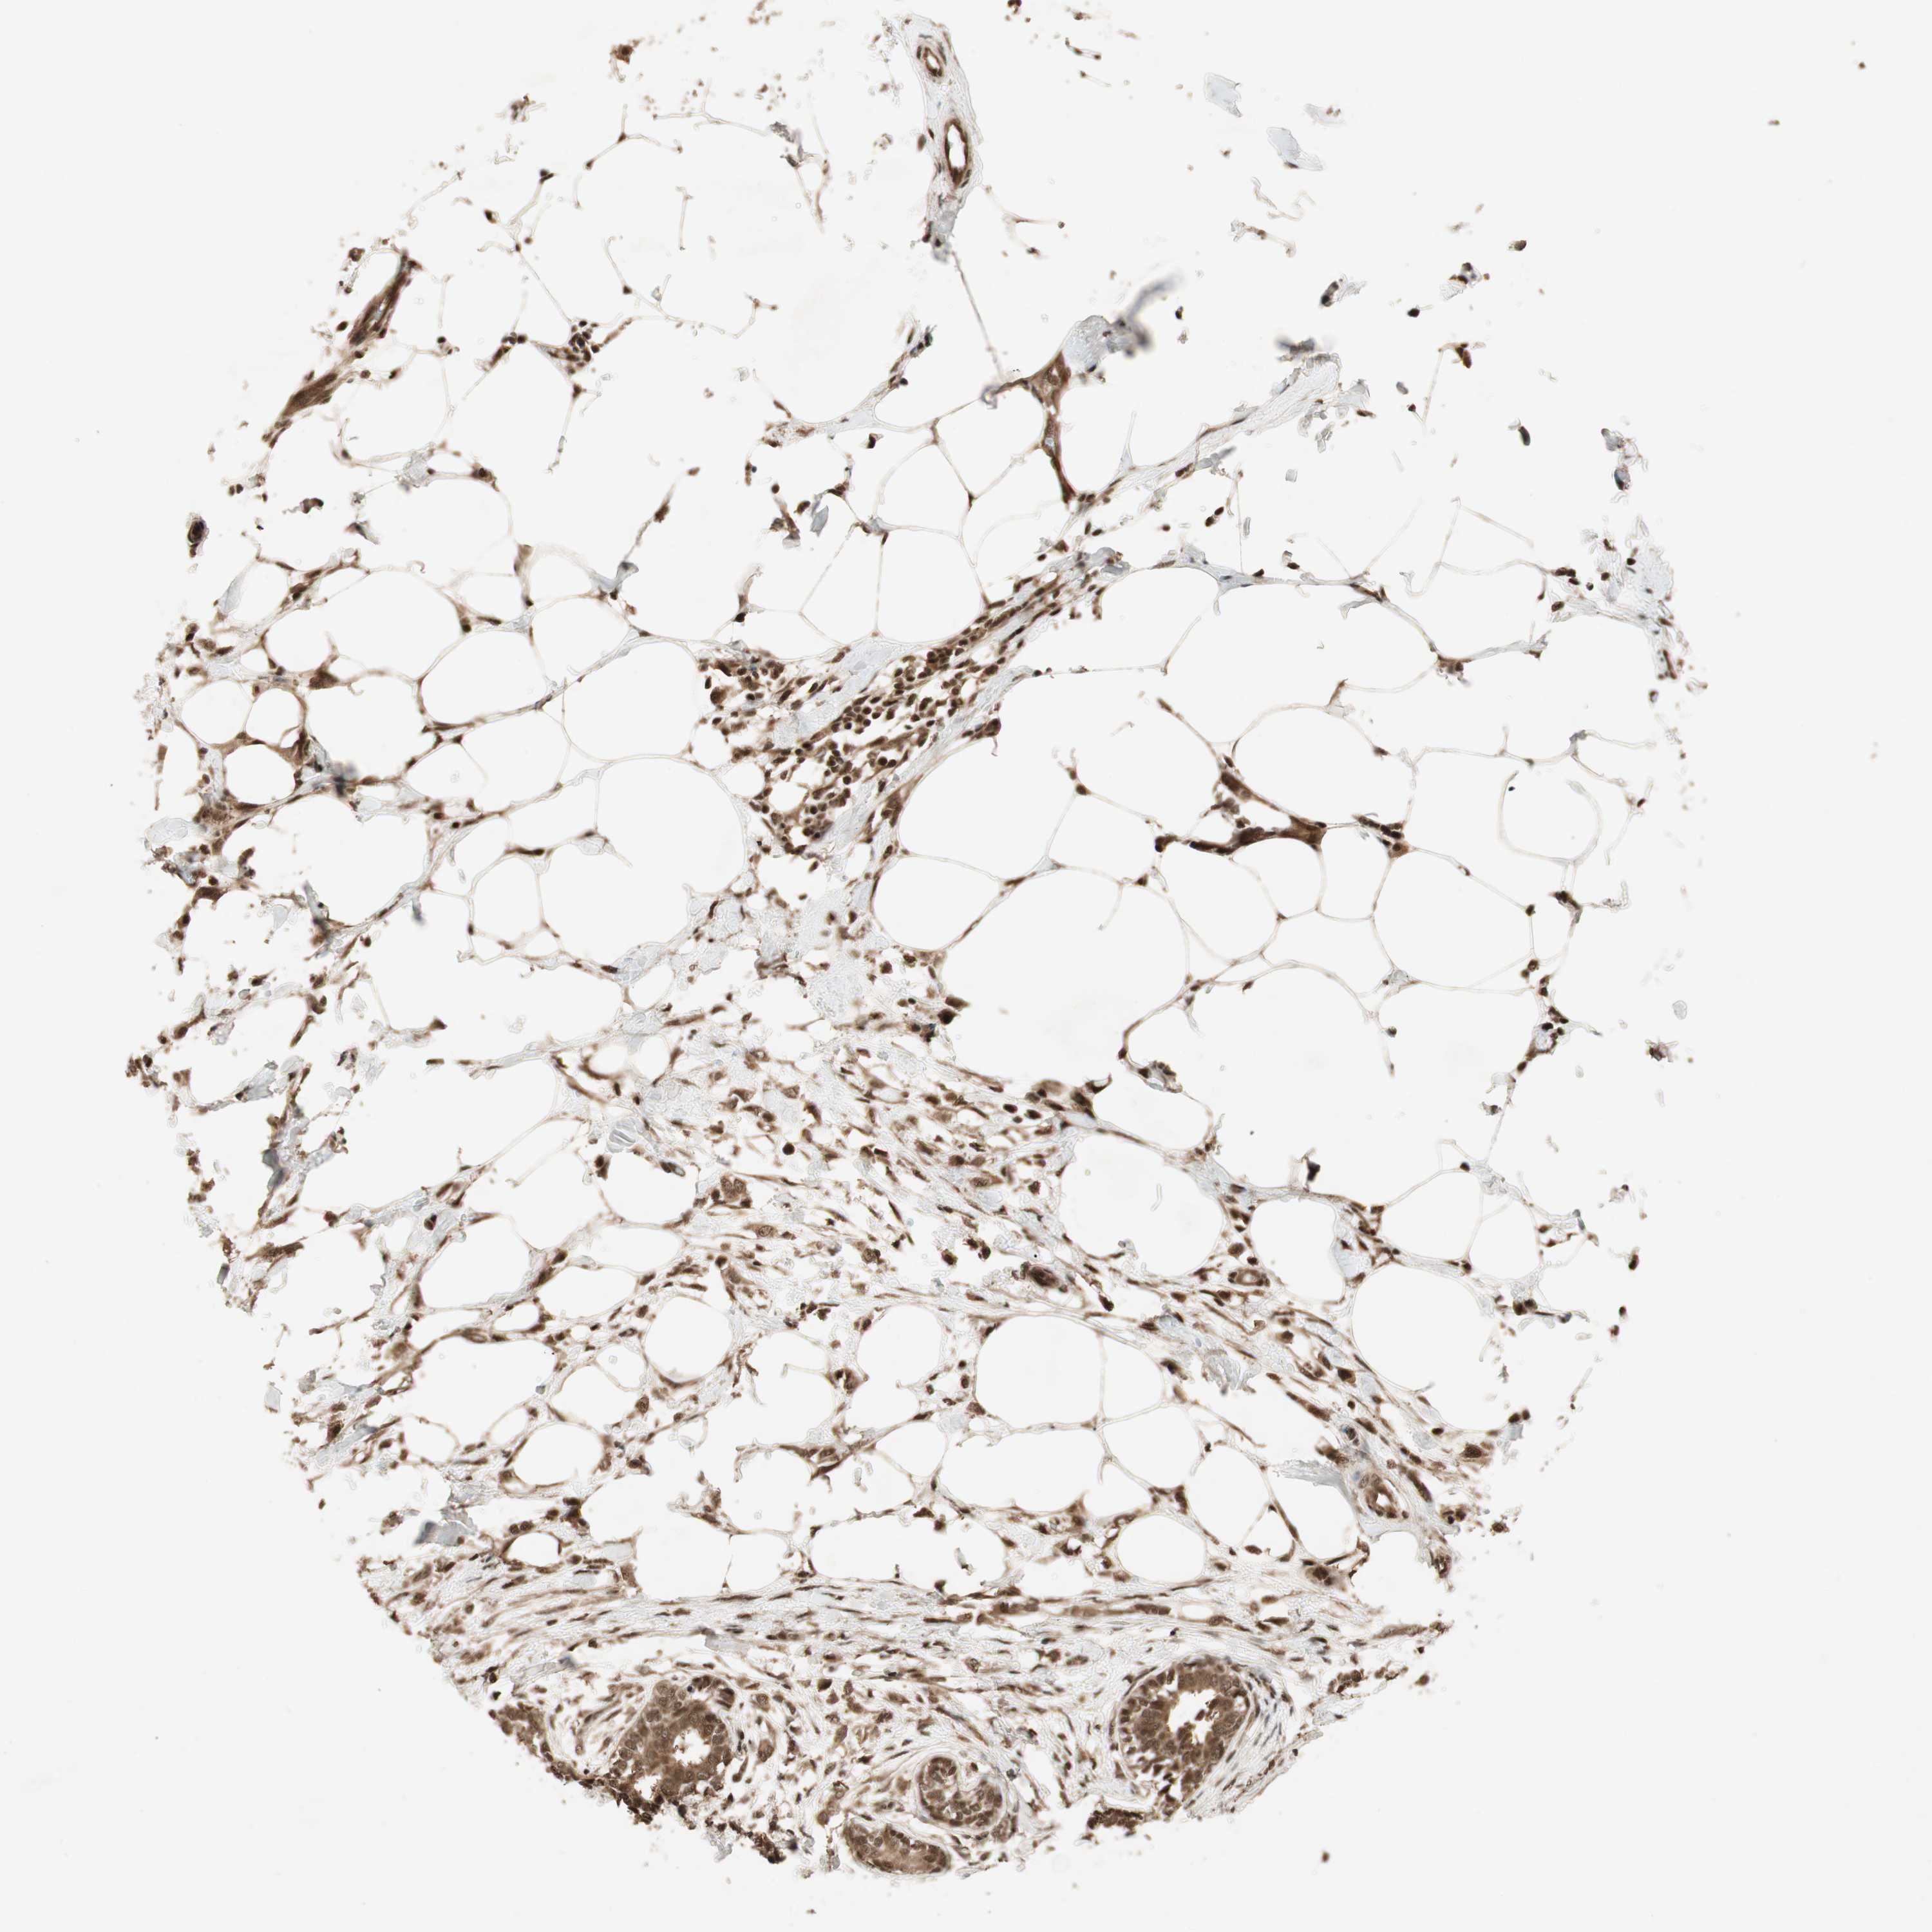

CANCER BREAST CANCER Show tissue menu

BRCA TCGA BRCA VALIDATION PROTEIN EXPRESSION

Breast cancer

Human cancer